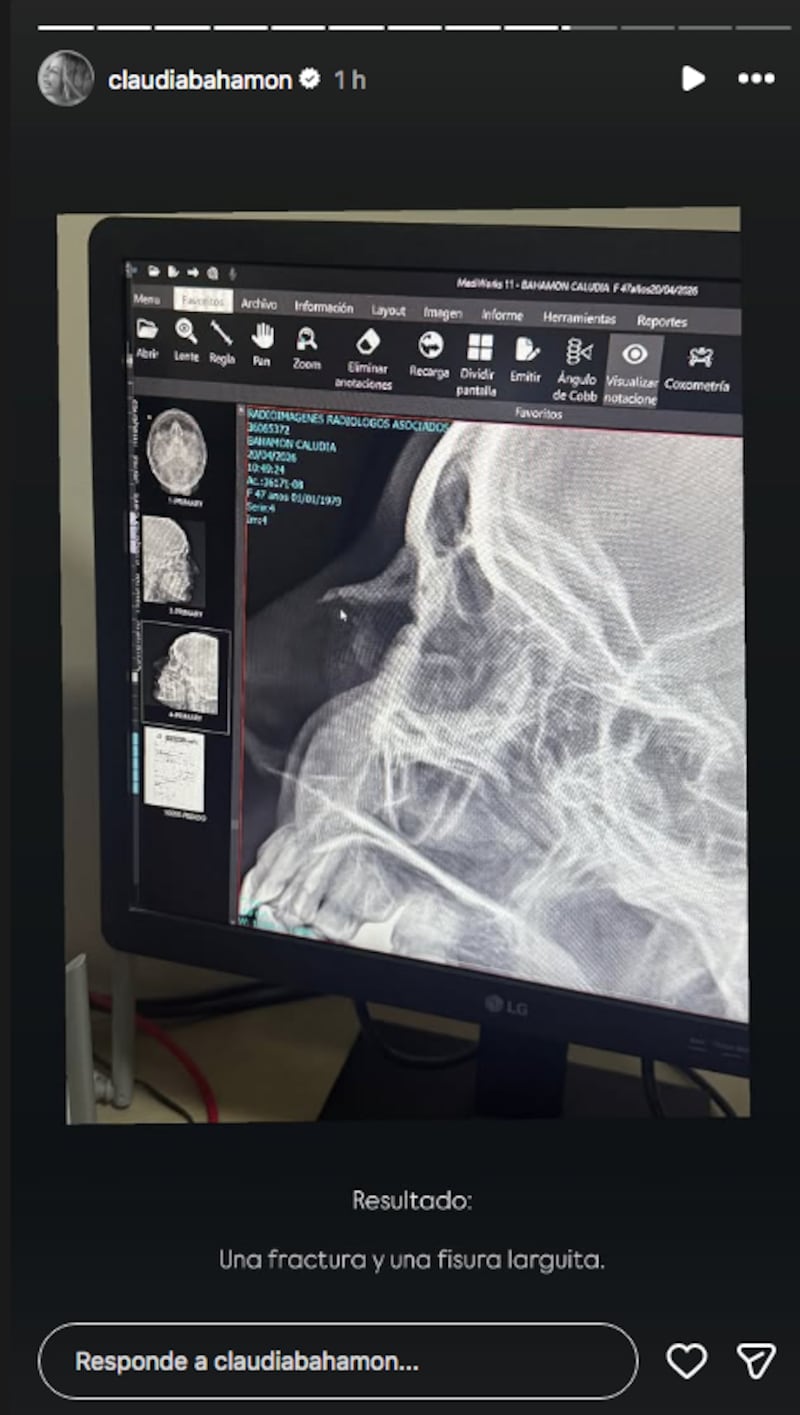

Más allá de su presencia en la televisión colombiana, Claudia también ha logrado alcanzar una amplia comunidad en las redes sociales, donde se encarga de compartir varios detalles de su vida. En medio de una de sus más recientes apariciones la presentadora de ‘MasterChef Celebrity’ confirmó una fractura en su naríz y una fisura.

De acuerdo con las declaraciones de Bahamón el accidente ocurrió mientras que estaba en una piscina nadando: “Sí me dio por creerme Phelps y se me achicó la piscina... y tas. Frené con la naríz. Estaba con este combo en Cartagena y dije a nadar (...) Y mi amiguita Pamela Puentes me graba y me dice, ‘amiguita esto no está bien. Mejor antes de grabar vamos a que te miren RX y otorrino’. Aterrizamos en Santa Marta y resultado una fractura y una fisura larguita". A pesar de lo ocurrido la presentadora de RCN sigue adelante con las respectivas grabaciones de ‘MasterChef Celebrity’.